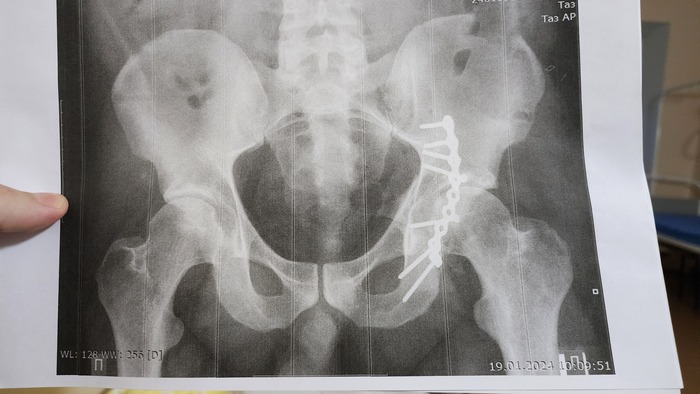

Всем привет, и так, моя эпопея с этим переломом наконец то кончилась, скажу сразу что все таки пришлось менять таазобедренный сустав. И так начнём все попорядку....... После продолжительных попыток хоть как то сохранить свой сустав, пришёл к выводу что это все как мёртвом припарка и начал искать себе врача и клинику, где мне бы могли его грамотно заменить. Очень много слышал от врачей что походи ещё немного, всегда успеешь его заменить, ты ещё молодой, и т.д и т.п, но самый веский аргумент в мою пользу был то что я попросту не мог нормально ходить, были дикие боли, прострелы и прочее, которые меня неустраивали от слова совсем, да и на работу с такой ногой я тоже не как не мог пойти(элементарно, не мог пройти комиссию). Предлагали множество вариантов по лечению асептического ннкроза типо тунелизации и прочих операций, которые в моем случаи представляли сомнительный результат и в итоге все равно приводили бы к протезированию! Так вот, нашёл я врача в городе Барнаул, там целый федеральный центр протезирования. Сначала позвонил туда и записался на приём по видеосвязи, где посмотрев предварительно мои снимки и результаты мрт решили менять сустав и не тянуть время. И вот ровно через год и один месяц после ДТП 22.01.2025 я поменял тазобедренный сустав. После операции я если честно просто охринел, меня подняли с кровати на следующий день и сказали пройтись по коридору на костылях, что у меня получилось просто великолепно( на большое удивление мне, ведь после первой операции я не мог встать около недели). Больница просто огонь, все добрые, ухаживают, присматривают! Ну и по итогу всего рассказа, сейчас прошло уже 9 месяцев, и я практически восстановился до того момента как было до ДТП. Есть конечно небольшой дискомфорт иногда, ну я думаю что это все терпимо. Вот так прошли мои 2 года после этой аварии. Люди будте внимательней на дорогах, не будет мудаками, очень хреновые вещи происходят когда машины врезаются, и очень неприятно когда в такие ситуации попадают люди не по своей вине, а ушлепки которые вылетают на встречку, остаются безнаказаными и сука более менее целыми!